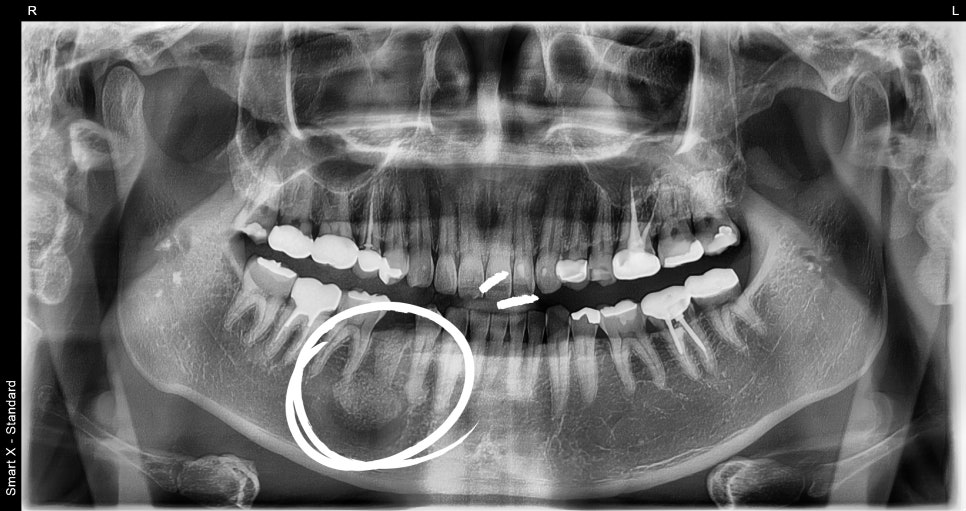

수술 후 관리 및 결과

✔️ 수술 직후 출혈 minimal, 합병증 없이 안정적 회복

✔️ 1주 후 실밥제거 시 통증, 부기 모두 조절 가능 수준

✔️ 병리결과: Odontogenic cyst (치성 낭종) / 양성 종양성 병소

✔️ 현재 치아 보존된 상태로 경과 관찰 중